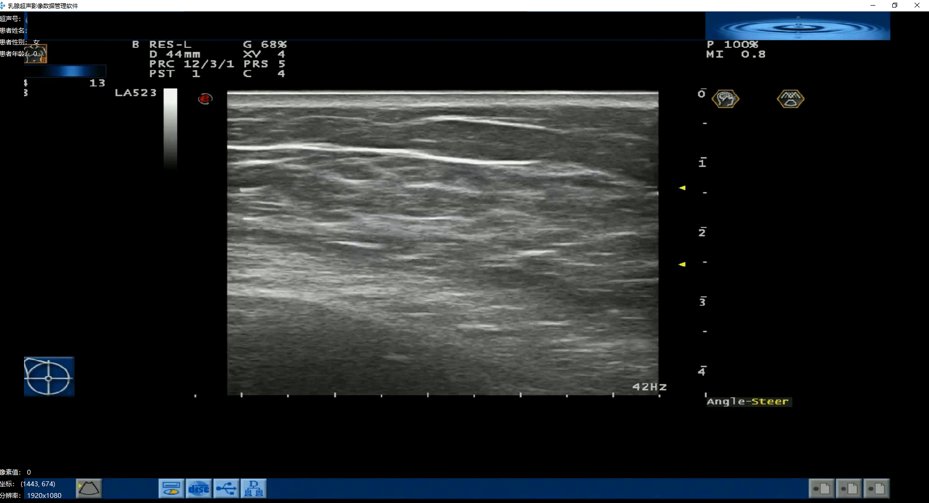

7月11日,医准智能在世界人工智能云端峰会上正式发布乳腺超声智能检测系统。该系统在不改变现有超声设备和医院工作流程的基础上,利用神经网络架构搜索方法(NAS)对超声信号进行实时智能分析,实现实时病灶检出,对病灶进行自动分割及良恶性分析。这是国内首款针对超声设备的视频AI检测系统,将乳腺智能检测推进到视频实时检测的AI 3.0时代。

医准智能乳腺超声智能检测系统不需要对设备改动,且不需要调整现有工作流程,在医生扫查病人的同时,AI服务器进行实时分析,并在界面进行标记提示,对于仅毫秒级闪现的病灶也能精准抓取,能够有效的避免医生由于视觉疲劳以及视觉敏感度不够而产生的漏诊。

系统采用神经网络架构搜索方法(NAS),使用RTX2080Ti。达到每秒处理速度>50帧,且检测结果延迟<0.09 秒,对于仅毫秒级闪现的病灶也能精准抓取。